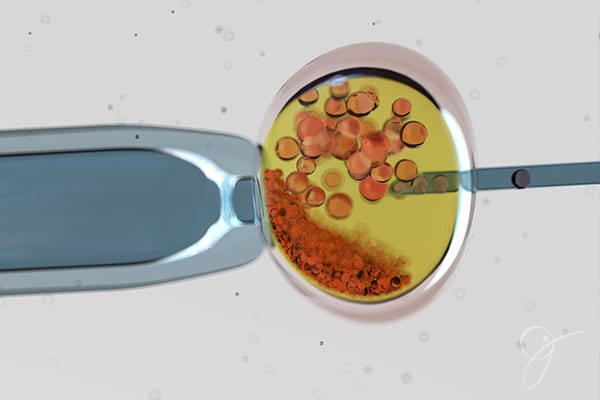

O teste genético pré-implantacional é feito obrigatoriamente durante um ciclo de FIV, especificamente na fase de cultivo embrionário. As etapas anteriores ao cultivo são a estimulação ovariana e indução da ovulação, a coleta dos óvulos e dos espermatozoides e a fecundação em laboratório. Os embriões formados são mantidos em ambiente controlado para que se desenvolvam por alguns dias.

No 5o dia de cultivo embrionário, o embrião está com aproximadamente 120 células (em estágio de blastocisto), momento ideal para a análise genética. Nessa ocasião, é realizada a biópsia, com extração de 5 a 6 células do embrião. O material genético coletado é enviado para análise e os embriões podem ser mantidos em desenvolvimento ou congelados. A análise pode ser feita em 24h e, assim, o embrião pode ser transferido no mesmo ciclo. Contudo, a análise mais detalhada exige um período de 7 a 10 dias para um resultado conclusivo. Nessa última situação, os embriões que passaram por biópsia são congelados e transferidos em ciclo posterior.

Dependendo da qualidade embrionária, podemos fazer a análise genética no 3o dia de desenvolvimento do embrião, mas existe um maior risco de danos ao embrião e o resultado é menos preciso, em virtude do pequeno número de células avaliadas. Essa conduta é indicada apenas em casos específicos, por exemplo de baixa qualidade embrionária, quando dificilmente o embrião se desenvolve em laboratório até o 5o dia.